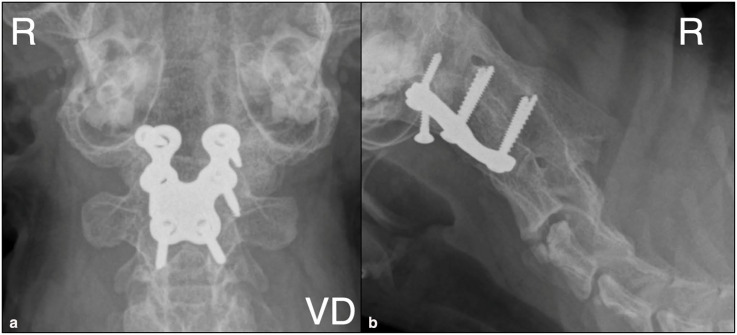

病例总结:本病例报告中描述的猫表现为进行性非活动性四肢全瘫。它被诊断为枕骨寰枢畸形(OAAM),导致严重的压缩性脊髓病。这种情况是由枕髁变平和椎体轴变短引起的。此外,在CT上观察到寰枢关节发育不良。这只猫接受了手术治疗,使用了一个板,这是在畸形的三维模型的帮助下定制的。手术后三周,这只猫能够在没有帮助的情况下行走;术后5年,猫的神经系统检查正常。相关性和新信息:使用三维技术的手术计划在复杂的OAAM病例中是有用的。这是第一个记录在案的猫科动物使用这种技术治疗这种疾病的病例。

Case summary: The cat described in this case report presented with progressive non-ambulatory tetraparesis. It was diagnosed with an occipitoatlantoaxial malformation (OAAM), which resulted in severe compressive myelopathy. This condition was caused by a flattening of the occipital condyles and shortening of the vertebral body of the axis. In addition, there was dysplasia in the atlantoaxial joint, which was observed on CT. The cat was treated surgically using a plate, which was custom-made with the help of a three-dimensional model of the malformation. Three weeks after surgery, the cat was able to walk without assistance; 5 years after surgery, the cat showed a normal neurological examination.

Relevance and novel information: Surgical planning using three-dimensional technology was useful in a complex case of OAAM. This is the first documented feline case that uses this type of technology for this condition.